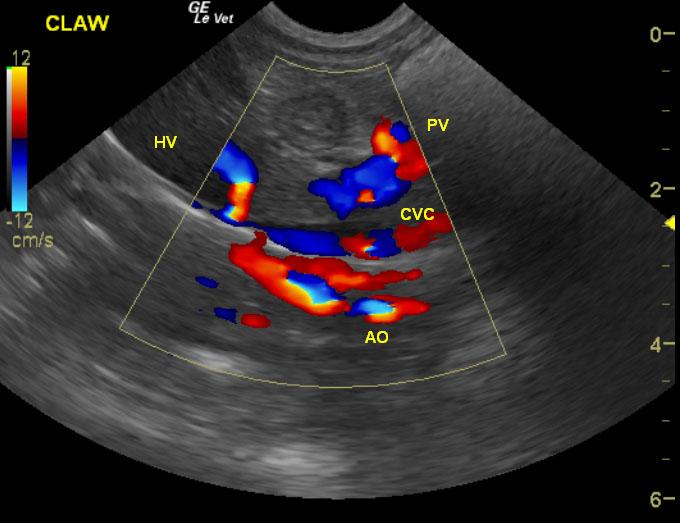

Exam of the cranial abdomen demonstrated normal liver size, contour, and structure. Parenchymal echogenicity was naturally coarse and hypoechoic to the spleen. Vascular and biliary tracts were of normal volume and no evidence of congestion was noted. The portal vein, caudal vena cava, and aorta were 0.6/0.56/0.6cm respectively revealing a PV:CVC and PV:Ao ratio of 1:1 ruling out the presence of extrahepatic shunts. The urinary bladder, trigone and pelvic urethra presented normal wall thicknesses with anechoic urine and normal tone. No uroliths or sediment were visualized.